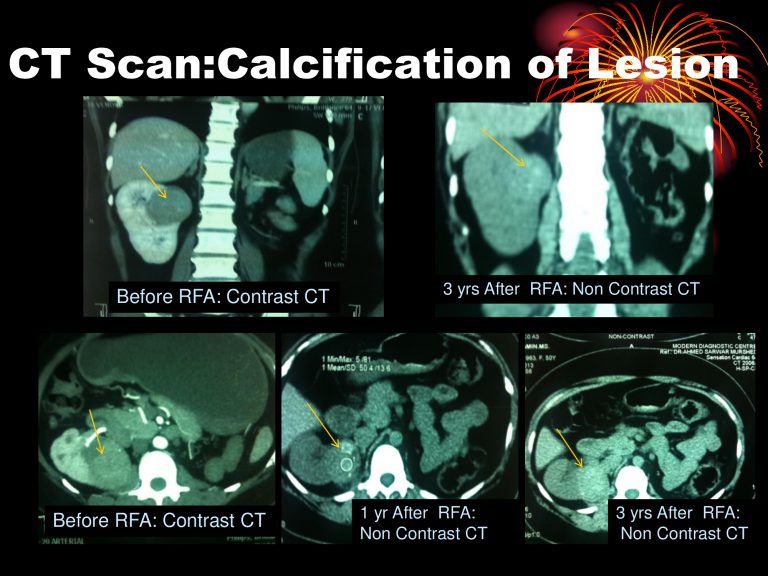

১) যাদের কিডনী ক্যান্সার টিউমার ৪-৮ সে.মিঃ তাদরে RFA, MWA দিয়ে চিকিৎসা মাধ্যমে ৯০%-৯৮% রোগীর ক্যান্সার সম্পূর্ন নিমূল করা সম্ভব। এছাড়াও যদি পুনরায় দেখা যায়,তবে আবার RFA, MWA চিকিৎসা করে ক্যান্সার টিউমার নিমূল করা যায়। ইদানিং বিভিন্ন ক্যান্সার সেন্টার ৪ সেমি. এর নীচের টিউমার গুলোর প্রাথমিক চিকিৎসা হিসেবে RFA বেছে নিচ্ছে। যাদের কিডনি ফেইলোরের সম্ভবনা আছে বা কিডনি নষ্ট হয়ে আছে তাদের জন্য RFA ভালো চিকিৎসা। যার ফলে কিডনি কে আরও ভালো রাখা সম্ভব এবং সুস্থ ও সাভাবিক জীবন যাপন সম্ভব।